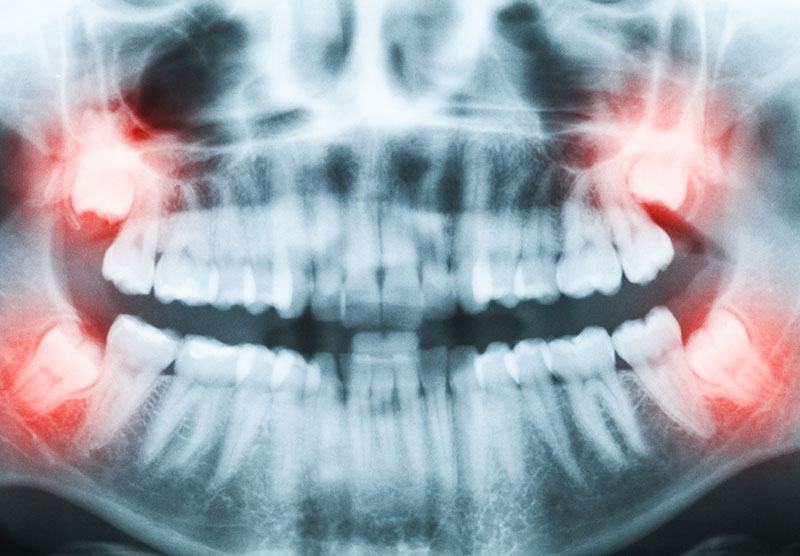

Un Panorex : Une radiologie de la bouche complète qui englobe les dents, les gencives et les racines des dents dans le but de détecter des problèmes spécifiques.

- 18-20 ans : un Panorex pour vérifier l’évolution des dents de sagesse

Une dent de sagesse qui demeure complètement ou partiellement incluse, demande une chirurgie pour qu’elle soit enlevée ou simplement qu‘elle soit aidée à pousser dans la bonne direction.

Si la dent de sagesse reste complètement incluse et tarde à faire irruption, cela peut occasionner des problèmes assez graves.